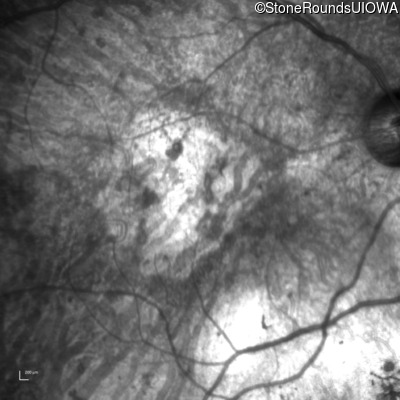

Infrared Fundus Photograph - Right - Hand Motion 1' sc

Exemplar